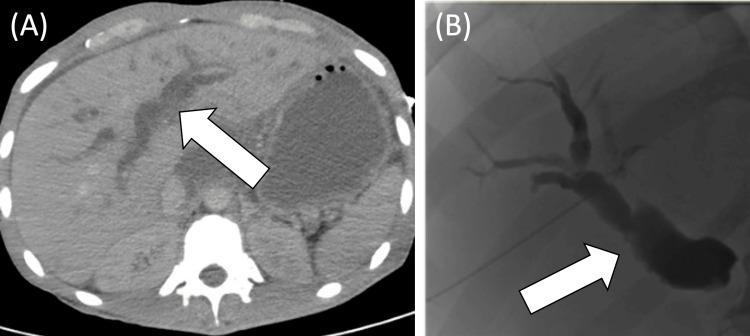

() is a gram-positive, facultative anaerobic bacterium that appears as cocci in chains and commonly causes skin infections and pharyngitis. Here, we present a very uncommon case of cholangitis associated with invasive infection in a 34-year-old man with metastatic pancreatic adenocarcinoma who presented with fever, right upper quadrant pain, jaundice, altered mental status, and hypotension. The patient underwent a percutaneous transhepatic cholangiogram, showing moderate dilatation of intrahepatic biliary ducts with obstruction of the proximal common bile duct, and an internal/external biliary drain was placed to allow for the flow of bile. Blood cultures grew . Biliary fluid culture obtained at the time of drain placement grew , , and . The patient was treated with ampicillin-sulbactam and fluconazole. While the patient recovered from his sepsis, he died within weeks of diagnosis due to complications of metastatic disease.

()是一种革兰氏阳性兼性厌氧菌,呈链状球菌,通常引起皮肤感染和咽炎。在此,我们报告一例非常罕见的胆管炎病例,该病例与一名34岁转移性胰腺腺癌男性患者的侵袭性感染有关,患者表现为发热、右上腹疼痛、黄疸、精神状态改变和低血压。患者接受了经皮经肝胆管造影,显示肝内胆管中度扩张,近端胆总管梗阻,并放置了内外胆管引流管以促进胆汁流动。血培养生长出……引流管放置时获得的胆汁液培养生长出……、……和……。患者接受了氨苄西林 - 舒巴坦和氟康唑治疗。虽然患者从脓毒症中康复,但由于转移性疾病的并发症,在诊断后数周内死亡。